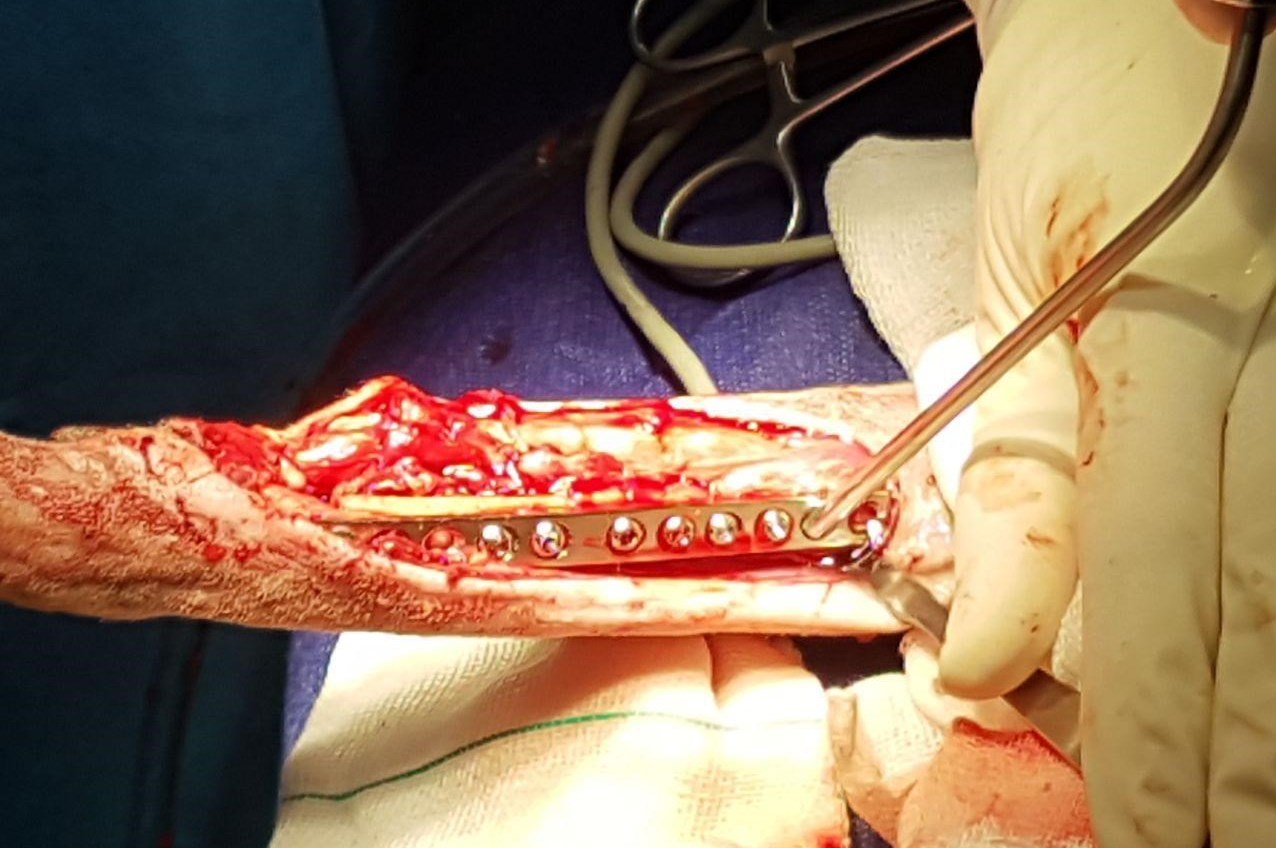

حمیدرضا فتاحیان جراح معالج شغال محمودآباد، درباره عمل جراحی این حیوان به خبرنگار اجتماعی خبرگزاری تسنیم گفت: شکستگی ساعد دست چپ این شغال ماده با استفاده از پیچ و پلیت، و شکستگی پای راست، به منظور تسریع در روند التیام شکستگی، با استفاده از پیچ و پلیت و همچنین پیوند استخوان تحت درمان جراحی قرار گرفت و در جهت کمک به روند درمان گچگیری شد. شکستگی استخوان پاشنه در مچ پای راست به دلیل وجود زخم در ناحیه مچ پای راست، مورد عمل قرار نگرفت که پس از بهبود وضعیت زخم در ناحیه مذکور و همچنین مشاهده وضعیت عمومی مناسب بیمار، در صورت نیاز به مداخله جراحی، در روزهای آتی تحت جراحی قرار خواهد گرفت.

گرفتن پیوند بافت اسفنجی از استخوان درشت نی شغال